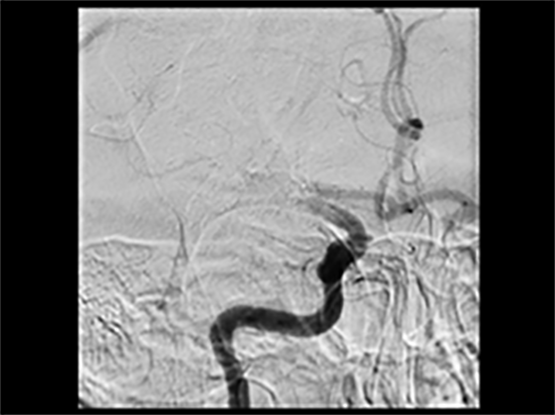

ET is performed by inserting a thin tube into the artery in the groin, through the body, and into the brain vessels to the clot. This is done under image-guided care using an X-ray. The clot is then removed by a retrievable stent and pulled out, restoring blood flow to the brain.